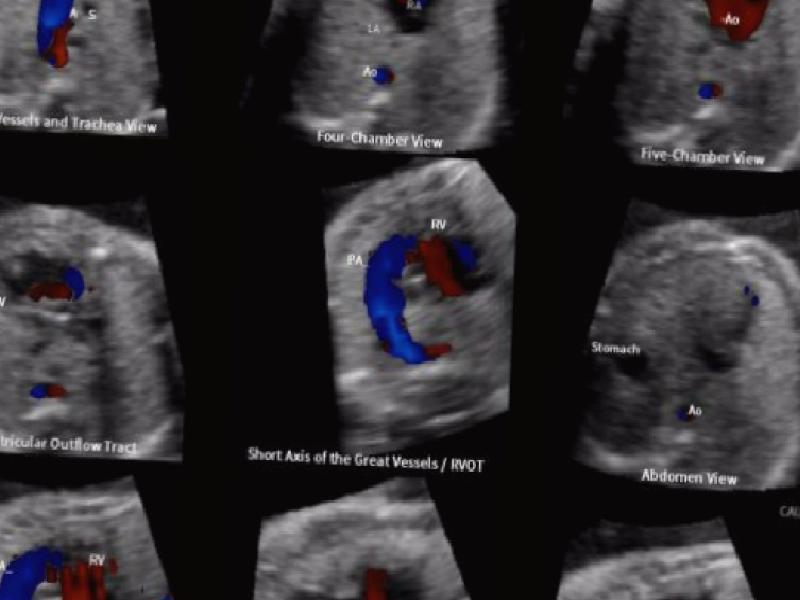

Fetal Echocardiography is an ultrasound method that can be performed from the 16th week of pregnancy and is performed on the abdominal skin of the mother. It is also called as “fetal echo” for short. It is a special ultrasound method that the Perinatology (Ridic Pregnancy) Specialist examines with special probes developed for the baby’s heart. Usually 18-23 weeks of pregnancy. It is performed during detailed fetal ultrasonography between weeks of However, if a suspicious finding is detected in the fetus, it can be performed in any period of pregnancy. With the use of color Doppler during the examination, the majority of “congenital heart diseases” of the baby in the mother’s womb can be diagnosed. Fetal echo, which is a special ultrasound method, has no harm or side effects to you or your baby. It can be applied at any time of the day without requiring a special situation such as hunger or satiety. The duration of ultrasound is 20-30 minutes on average, depending on some factors such as the position of the baby, its position in the womb, whether it is active and mobile, the location of the baby’s partner (placenta), the weight of the mother, and the structure of the abdominal wall. Fetal echocardiography is particularly recommended. These;